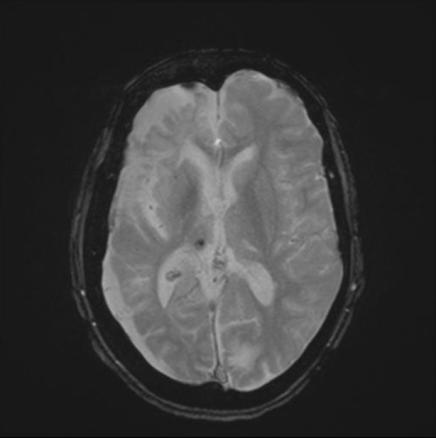

IRM cérébrale, coupe axiale. Le scanner cérébral montre une atrophie hémisphérique droite non connue, une lacune thalamique gauche et une surcharge athéromateuse des carotides.